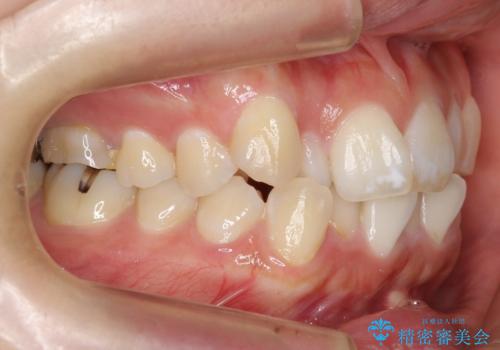

真ん中が右にずれている 前歯のがたつき 治療途中に地方へ引っ越したが、通ってワイヤー矯正

- 前歯のがたつきを主訴に来院。

前歯のクロスバイト、上の前歯の正中が右にずれていました。

右上の奥歯の高さもない状態でしたが、矯正治療が終わってからしっかりかぶせました。

上下左右の小臼歯を抜歯しています。